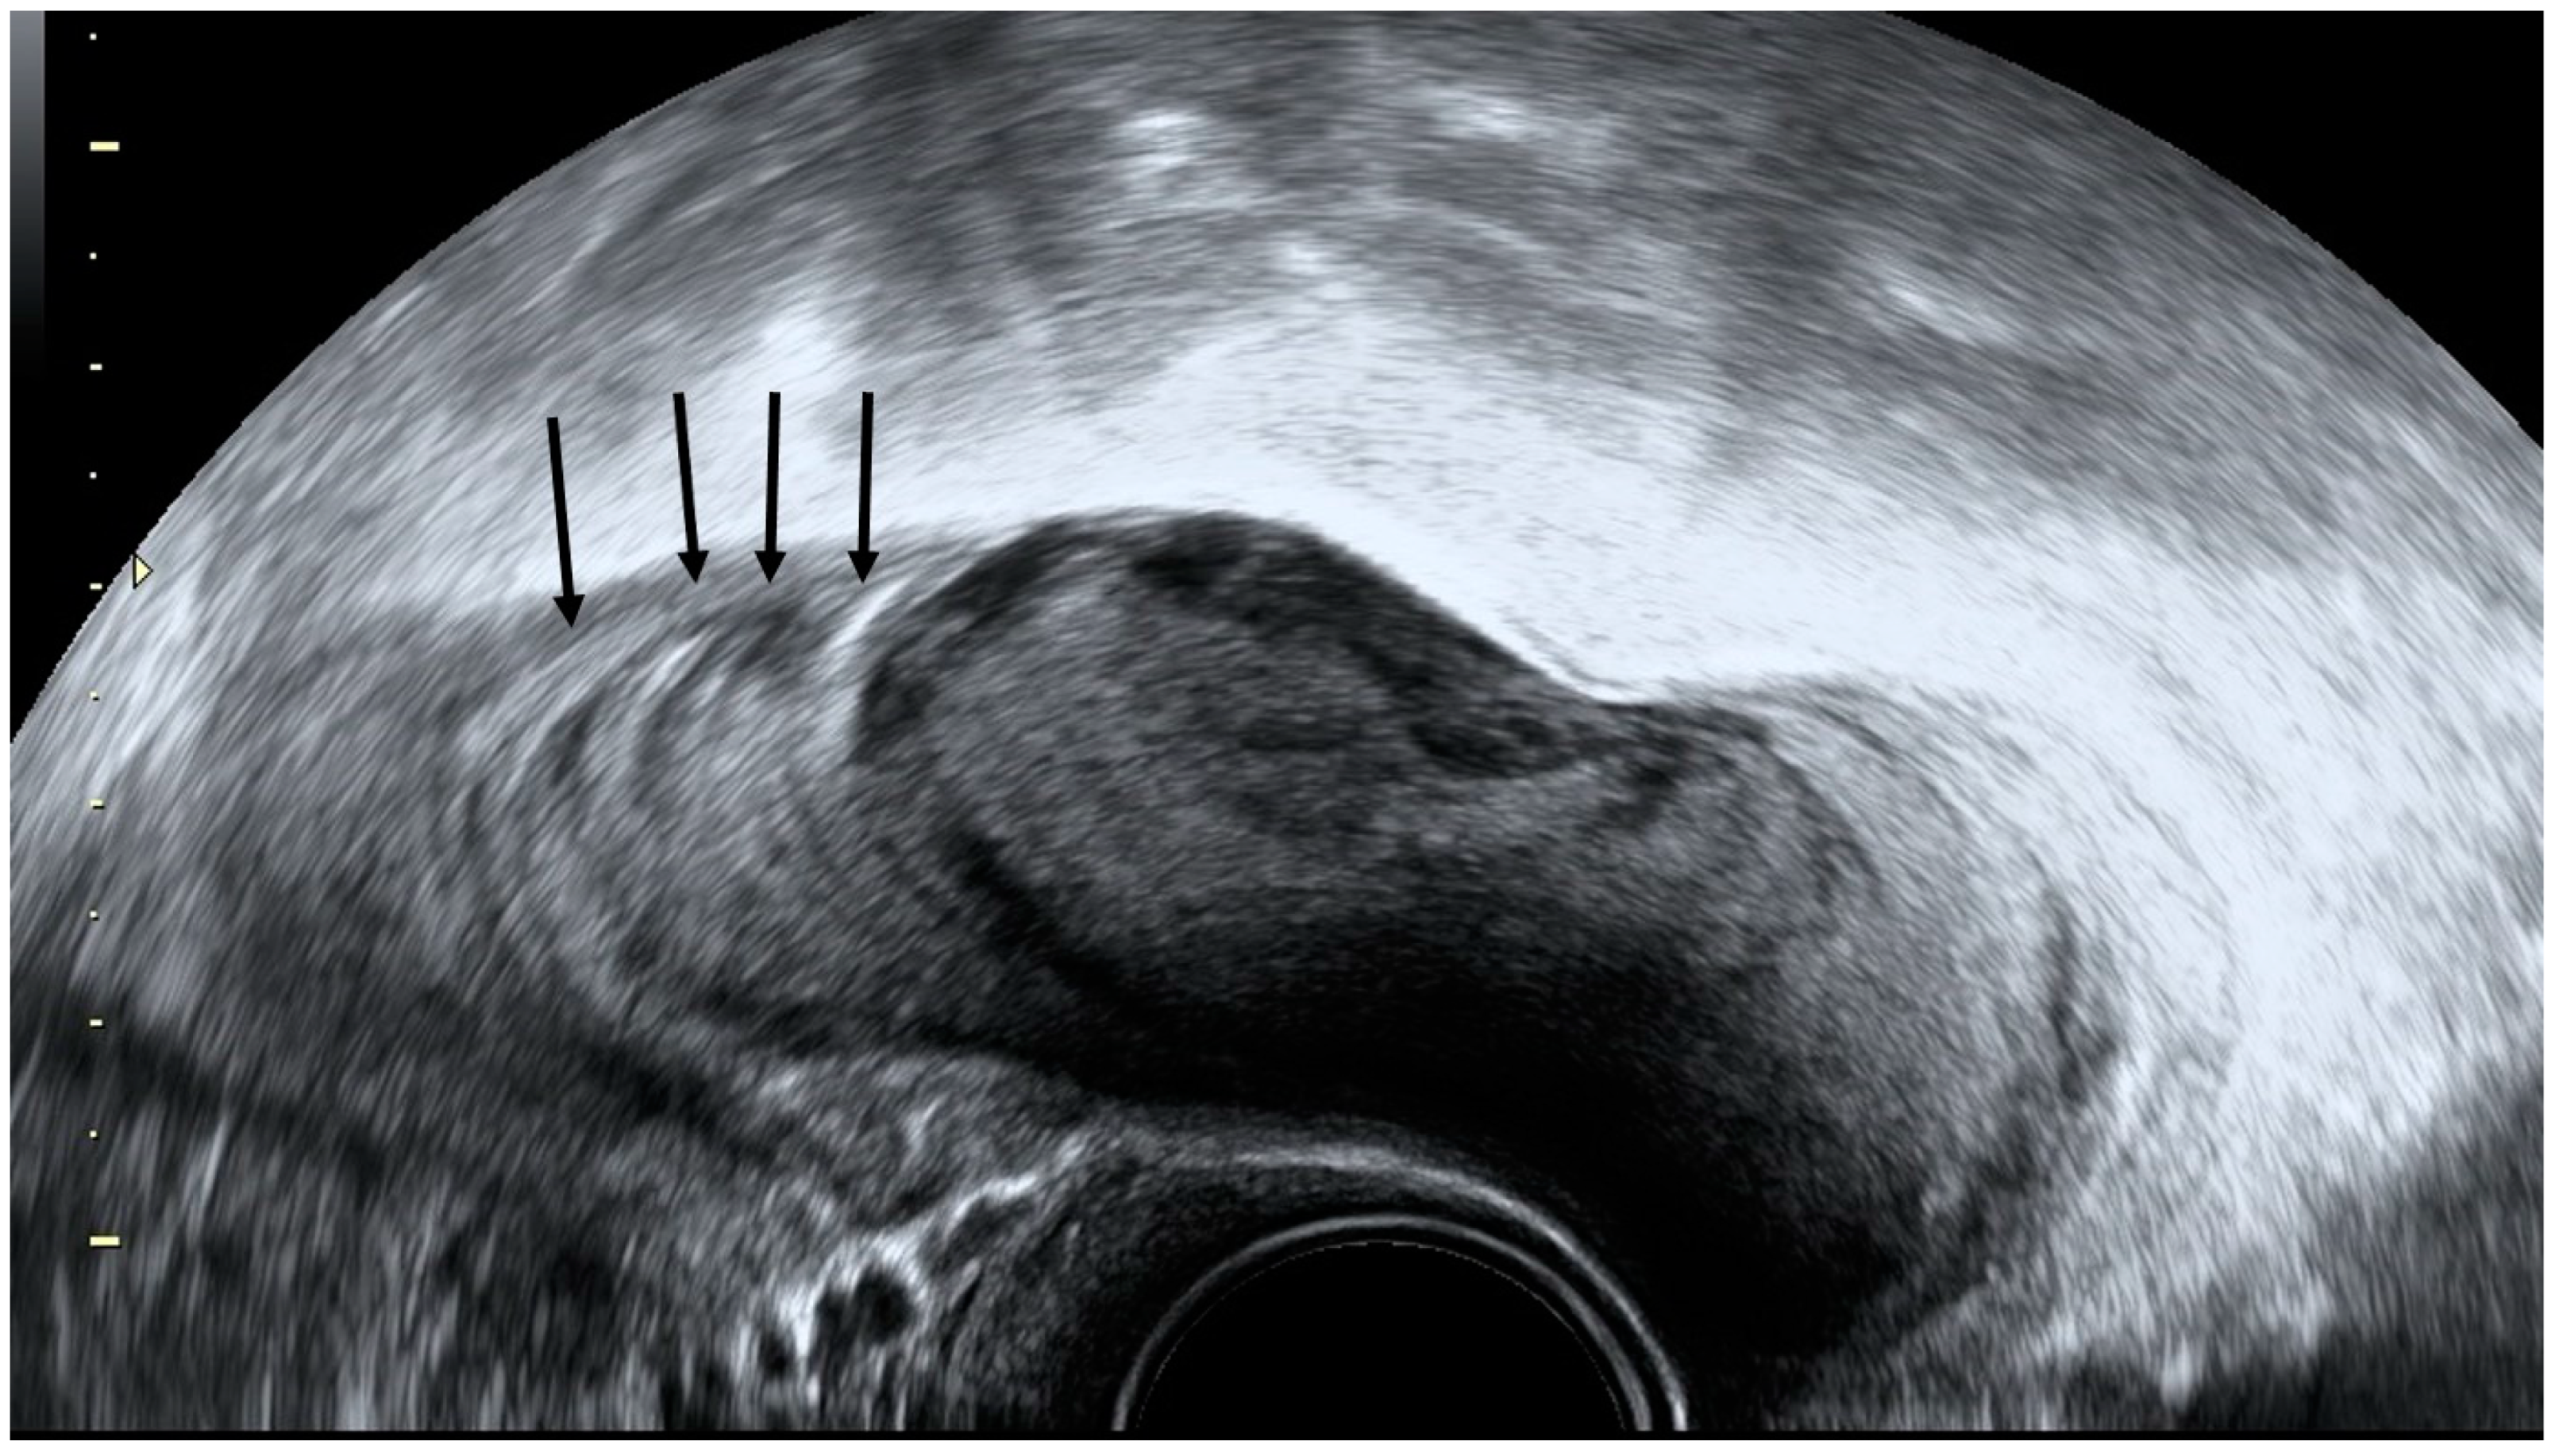

4.1. Pelvic Congestion